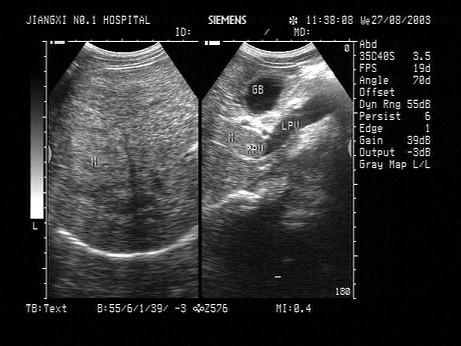

问题 根据以下肝超声检查声像图,诊断为?(?)

选项 A.肝癌并门脉癌栓 B.肝硬化 C.脂肪肝 D.肝炎 E.血吸虫性肝硬化并门脉血栓

答案 A